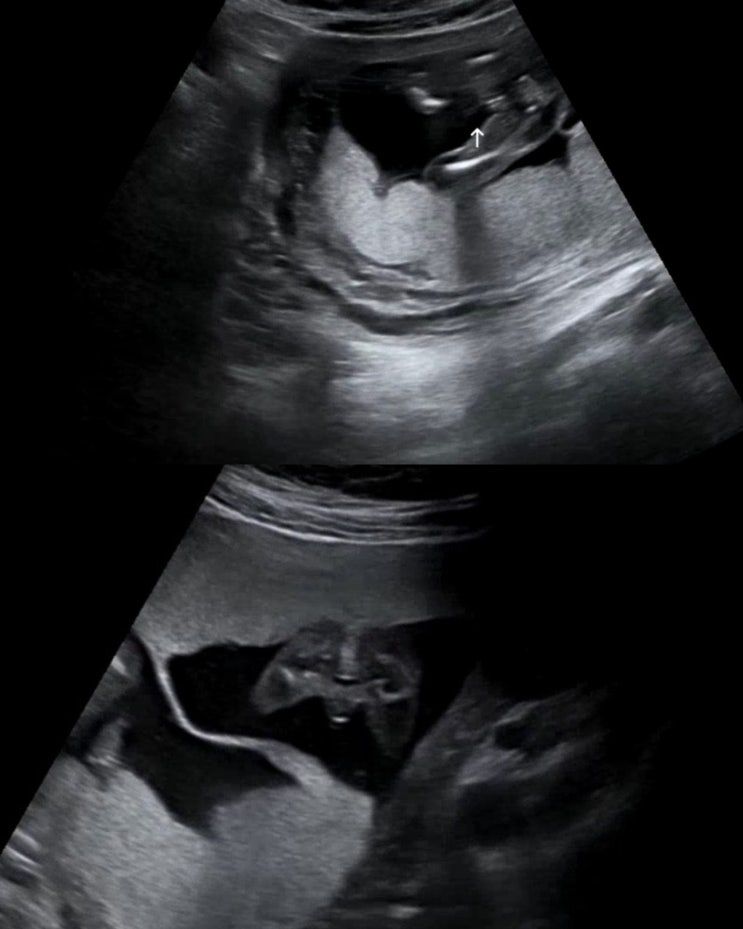

쌍둥이 12주, 16주 각도법 반전 (아들➡️딸 성별반전?)|장꾸맘의 각도법

초기가 지나고 중기가 되면서 가장 궁금해지는 게 하나 있을 거예요. 바로 '성별' ෆ 저는 다태...